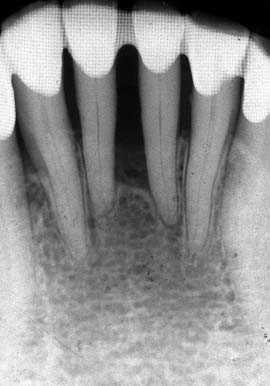

(図6)初診から33年経過(2008年1月7日)、71歳。咬耗は進んでいるが、骨植は堅固である